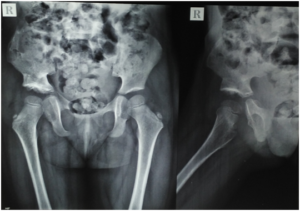

Parents came to me with their 1.5 yr old kid with limping (right side). After medical investigation, I found her right hip dislocated. She also had problems of ligamentous laxity.

In medical practice, there is no standard guideline to deal with congenital dislocation of hip with ligamentous laxity. So, I counselled parents for all possible options and went for major operation.

I asked them to come for regular follow ups. But they were lost to follow up. After 1 year, they came again with the following…

congenital-hip-dislocation-xray